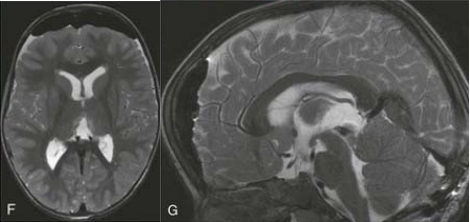

3岁患儿因典型的Parinaud综合征就诊,影像学证实为顶盖区神经胶质瘤延伸至第三脑室后部。若不及时干预,这种眼球运动障碍很可能进展为永久性残疾。手术团队采用小脑上幕下入路,在有限的解剖空间内精细操作,最终实现肿瘤全切除。令人欣慰的是,术后数月内患儿的眼球运动功能获得显著改善。

术前MRI

术后MRI